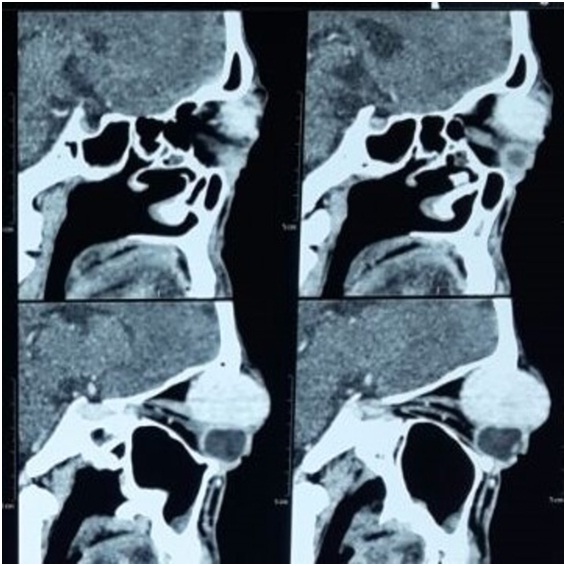

Computed tomography of the left orbit showed a 4.3x3.7x2.8cm sized homogeneous enhancing hyperdense lesion in the superior compartment of the left orbit originating in the extraconal compartment and extending intraconally, causing marked proptosis. The mass was seen distorting the globe and causing scleral buckling, most marked superolaterally [Table/Fig-2,3 and 4]. The fat planes with the optic nerve, sclera, lateral rectus, superior rectus, inferior oblique muscle were focally lost. It showed thinning but no erosion of roof of the left orbit. The differential diagnosis given upon imaging was: lacrimal gland tumour, nerve sheath tumour or atypical cavernous haemangioma.

Axial view of contrast computed tomography scan showing marked proptosis of left eye.

Sagittal view of contrast computed tomography scan showing homogenous enhancing lesion in extraconal compartment extending intraconally and distorting the globe.